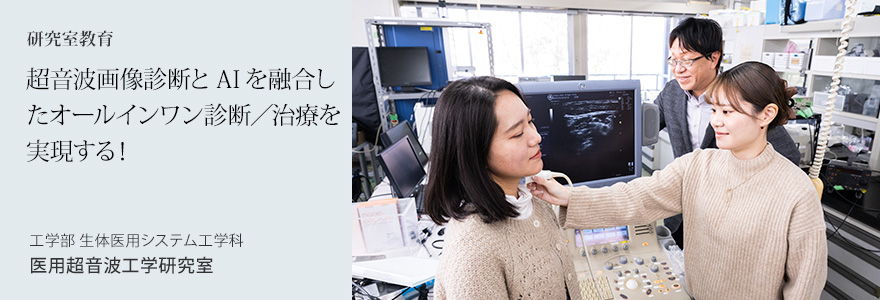

研究室には最新の超音波画像診断装置が設置されており、いつでも生体画像データを収集できる

研究室には最新の超音波画像診断装置が設置されており、いつでも生体画像データを収集できる現在、力を入れているのは、超音波医療へのAI応用です。AI技術の一つである機械学習を用いて、超音波画像診断の精度を向上させたり、必要な画像情報を自動検出したりする技術を開発しています。医療機関や医療機器メーカーとの共同研究も積極的に行っています。もともと日系メーカーの超音波画像診断装置は世界をリードする存在です。超音波のみを用いた診断/治療装置を日本の新たな産業として育て、輸出産業にまで発展させることが夢です。

桝田研究室では、多数の女子学生が活躍中

桝田研究室では、多数の女子学生が活躍中